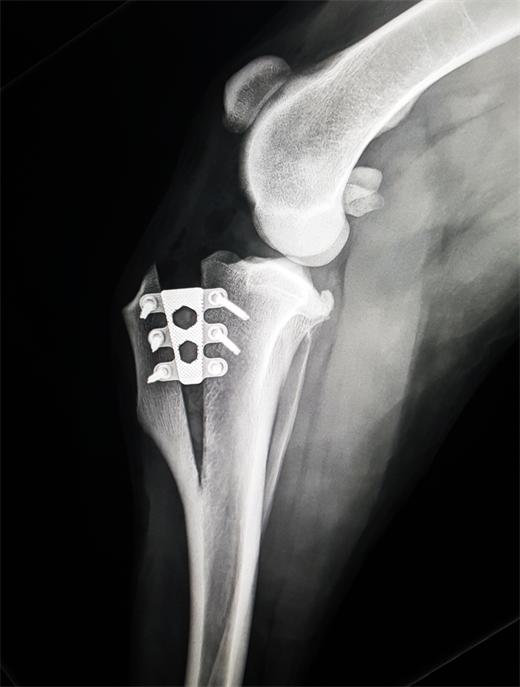

TTA X-Ray_Right Leg PO (Carolien Huismann-Wildeman)_2023 Catalog_This one-day practical course focuses on the TTA Rapid procedure for cruciate repair, including techniques for addressing patella luxation concurrently.

Geared towards veterinarians interested in mastering the TTA Rapid technique, this practical course includes sawbones and wet lab sessions for hands-on learning. Participants will discuss diagnosing cruciate ruptures, preoperative planning, surgical guidelines, and potential complications and solutions. The course will also explore unique methods for treating patella luxation simultaneously, providing ample opportunities for questions and hands-on practice.